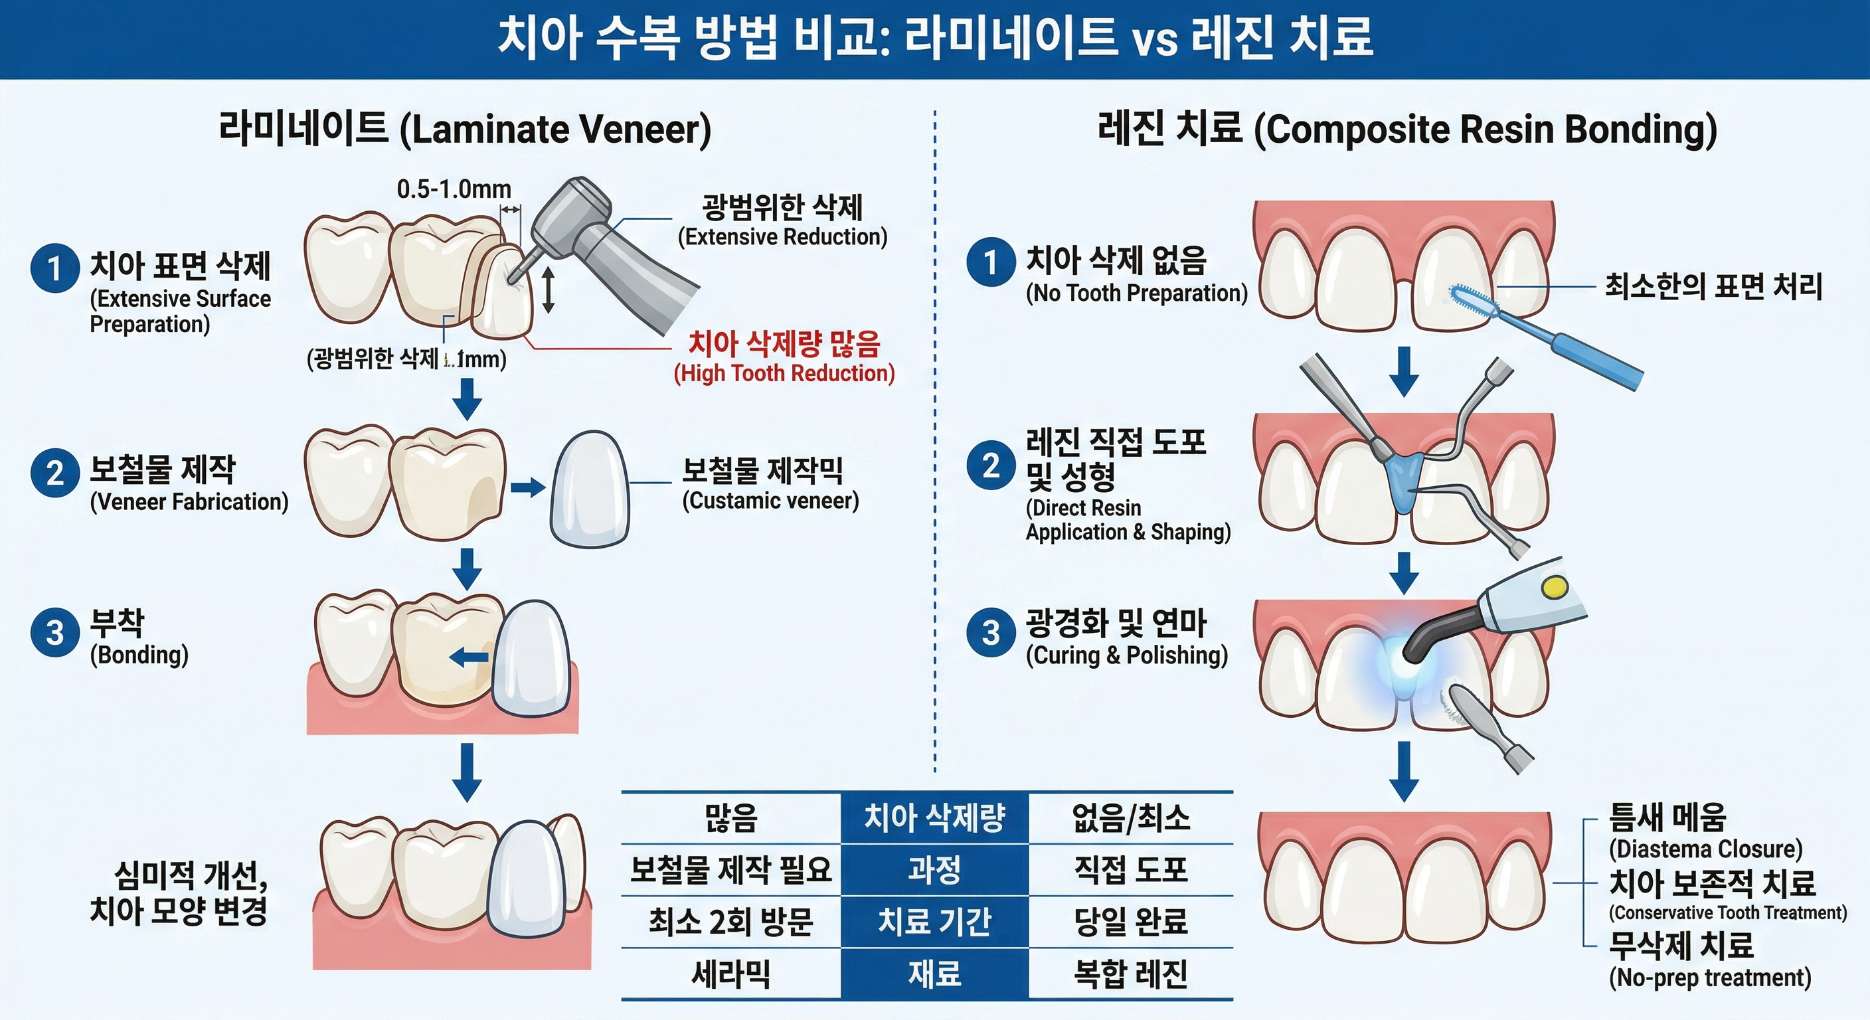

벌어진 앞니를 해결하는 방법 중 하나인 라미네이트나 크라운은 심미성이 매우 뛰어나지만, 치아 표면을 일정량 깎아내야 하므로 한 번 삭제한 치아는 영원히 자연 상태로 되돌릴 수 없다는 치명적인 단점이 존재합니다.

반면 ‘틈새 레진’은 치아를 전혀 삭제하지 않거나 접착력을 위해 표면만 극미세하게 다듬은 뒤, 치아 색상과 완벽하게 동일한 치과용 고분자 수지(Resin)를 빈 공간에 덧붙여 메우는 가장 보존적인 치료입니다. 비용적인 가성비가 훌륭할 뿐만 아니라 소중한 자연치아를 100% 지킬 수 있는 안전한 선택지입니다.

틈새 레진 치료의 가장 강력한 장점은 수개월이 걸리는 교정과 달리 단 ‘하루’, 약 1~2시간 내외의 진료만으로 모든 과정이 드라마틱하게 끝난다는 것입니다.

치아 표면을 미세하게 산 처리(Etching)하여 깨끗하게 만든 후, 특수 접착제(Bonding)를 바르고 다양한 투명도의 레진을 치아의 결에 맞춰 여러 겹으로 정교하게 쌓아 올립니다(Layering technique). 이후 광중합기로 단단하게 굳히고 원래 내 치아처럼 자연스럽게 굴곡을 다듬는 폴리싱(Polishing) 과정을 거치면, 웨딩 촬영 전날 방문하셔도 감쪽같은 미소를 완성할 수 있습니다.